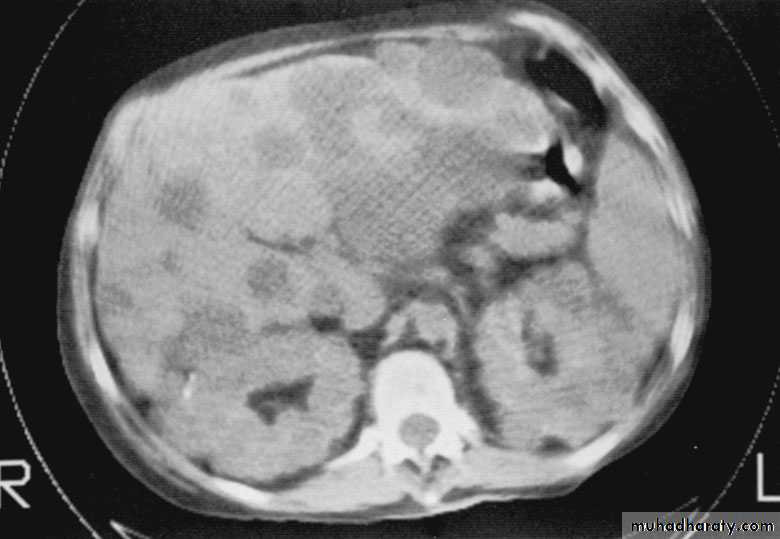

Congenital cystic kidney (polycystic kidney) (Adult cystic renal disease)

Autosomal dominant, transmitted by either parents, 50% of offspring affected.

Both kidneys replaced by large no. of cysts of variable size which make the kidney of large size.

The cysts contain clear fluid but sometimes blood.

The cysts progressively increase in size causing pressure atrophy of the renal parenchyma and pressing the ureter.

15% associated with cystic disease of liver, lung, pancreas or spleen.

Clinical pictures:

Rarely gives clinical manifestation before 4o years

Asymptomatic: diagnosed accidentally.

Pain: due to pedicle stretching, stone, ureteric obstruction, bleeding inside cyst or infection.

Hematuria: cyst distention and rupture to the collecting system.

Infection: renal or cyst infection causes fever, rigor and loin pain.

Hypertension: in 70%, Unknown cause.

Renal impairment: anorexia, headache, nausea, vomiting, drowsiness and coma.

Renal enlargement: large knobby palpable kidney

Diagnosis: Family history of polycystic disease.

U/S, IVU, CT scan, MRI